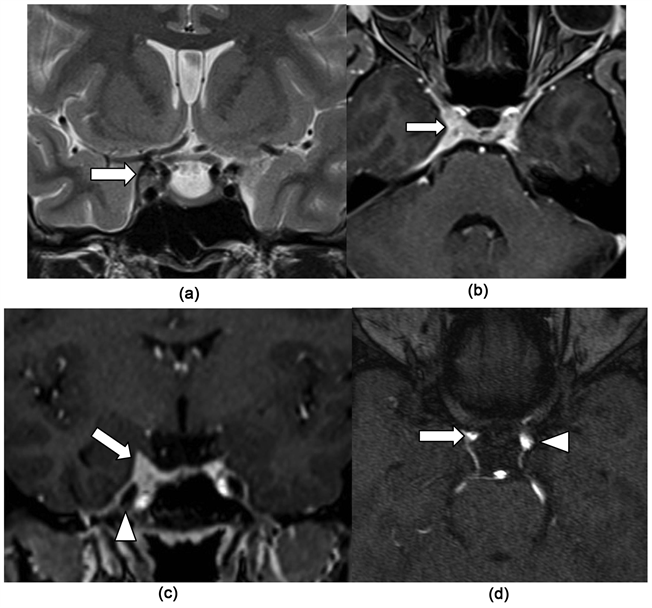

She had undergone a high field MRI (siemens 1.5T) with T1, T2, FLAIR, T2*, diffusion B1000, TOF polygon, CISS 3D and T1 gadolinium sequences in the 3 space planes. Exploration had found an enlarged right cavernous sinus, with a soft tissue infiltration that appears isosignal T2 SE on Figure 1(a). Its involvement is compared to the left side, which is normal. The lateral wall of the sinus appeared hyposignal and was well identified on the same figure. Global morphology of the cavernous sinus and the Meckel’s cavum were respected as showed on Figure 1(c). The lesion was strongly enhanced after gadolinium

Figure 1. Coronal T2 SE (a) showing an isointense thickening of the right cavernous sinus (arrow (a)) compared to the left normal (arrowhead (b)); Axial T1 gadolinium (b) showing strong diffuse contrast enhancement of the right cavernous sinus without (arrow (b) and (c)); Coronal section T1 after gadolinium injection, showing the lesion that let intact the Meckel’s cavity (arrowhead (c)); TOF axial native section (d) showing a significant mass effect on the right internal carotid (arrow (d)) compared to the left internal carotid (arrowhead (d)).

injection on Figure 1(b) and Figure 1(c). There was also a slight compression of the intracavernous ipsilateral internal carotid on Figure 1(d). These aspects pleaded for a diffuse inflammatory involvement.

Involvement of the cavernous sinus and the superior orbital fissure in the THS appears as a diffuse infiltration isosignal on T2 weighted sequence with enlargement of the cavernous sinus [Figure 1 and Figure 2] [5] [6] [7] [8] [9] . After gadolinium injection, there is a diffuse and significant enhancement that reaches the neighboring regions such as the orbital apex or the superior orbital fissure. Sometimes it is associated with a contrast enhancement of the adjacent pachymeningeal structures as noted on Figure 2.

Carotid involvement is part of the original description of Tolosa. It seems to be a characteristic [3] [4] [5] [6] that can be related to compression by the granuloma and/or vasculitis substantially reducing the carotid lumen as observed in our patients [Figure 1 and Figure 2]. Carotid involvement seems not to have any major encephalic consequence such as ischemia throughout literature. So there was in our patients.